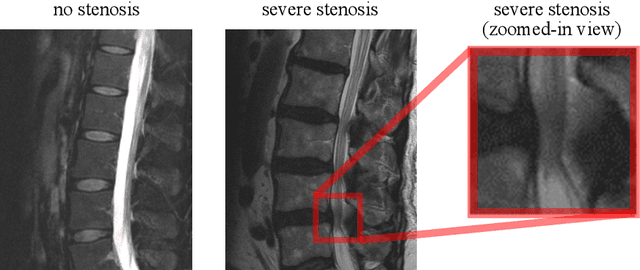

Abstract:The regulatory approval and broad clinical deployment of medical AI have been hampered by the perception that deep learning models fail in unpredictable and possibly catastrophic ways. A lack of statistically rigorous uncertainty quantification is a significant factor undermining trust in AI results. Recent developments in distribution-free uncertainty quantification present practical solutions for these issues by providing reliability guarantees for black-box models on arbitrary data distributions as formally valid finite-sample prediction intervals. Our work applies these new uncertainty quantification methods -- specifically conformal prediction -- to a deep-learning model for grading the severity of spinal stenosis in lumbar spine MRI. We demonstrate a technique for forming ordinal prediction sets that are guaranteed to contain the correct stenosis severity within a user-defined probability (confidence interval). On a dataset of 409 MRI exams processed by the deep-learning model, the conformal method provides tight coverage with small prediction set sizes. Furthermore, we explore the potential clinical applicability of flagging cases with high uncertainty predictions (large prediction sets) by quantifying an increase in the prevalence of significant imaging abnormalities (e.g. motion artifacts, metallic artifacts, and tumors) that could degrade confidence in predictive performance when compared to a random sample of cases.